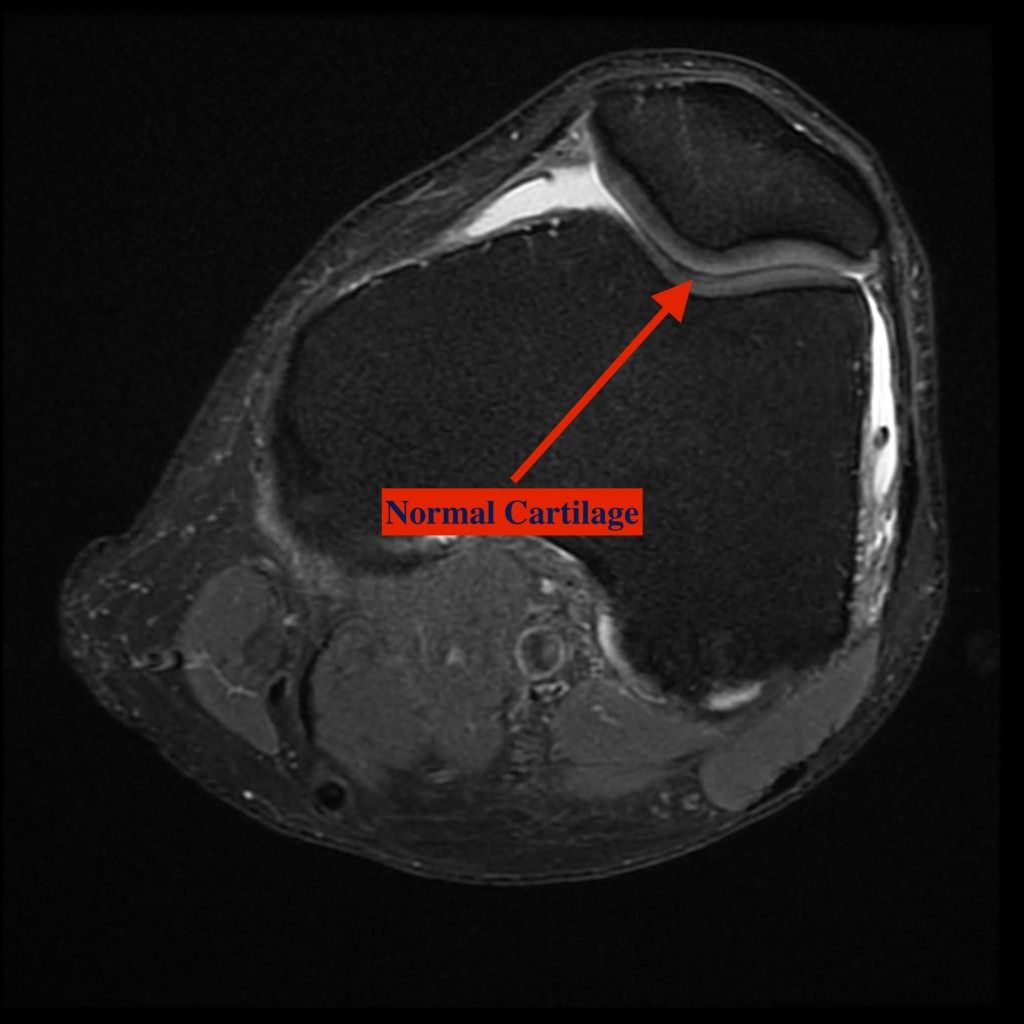

Patellofemoral arthritis occurs when the articular cartilage along the trochlear groove and on the underside of the patella wears down and becomes inflamed. When cartilage wears away, it becomes frayed and, when the wear is severe, the underlying bone may become exposed. Moving the bones along this rough surface may be painful.

Cartilage grafting. Normal healthy cartilage tissue may be taken from another part of the knee or from a tissue bank to fill a hole in the articular cartilage. This procedure is typically considered only for younger patients who have small areas of cartilage damage.